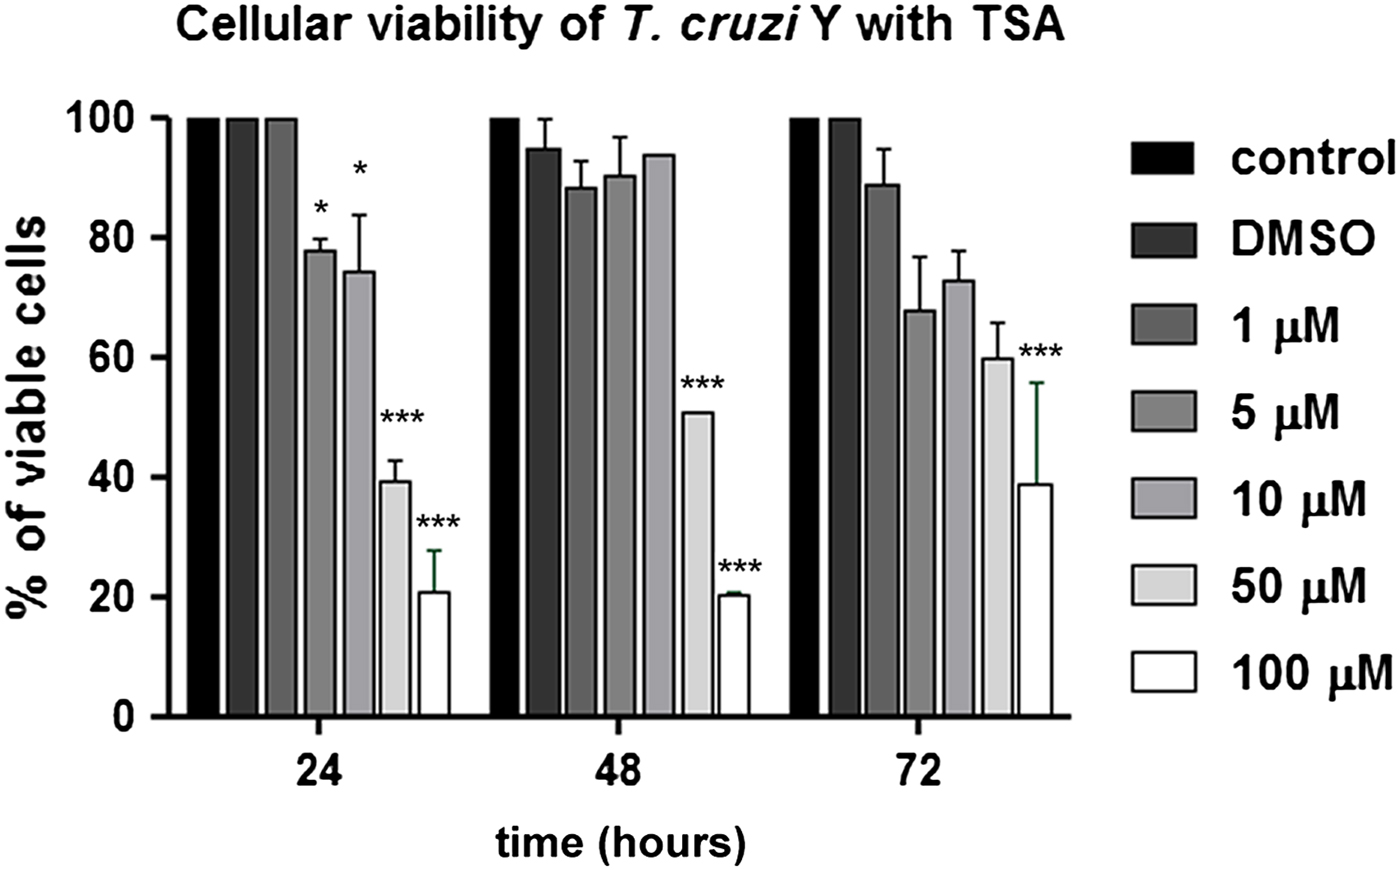

Concerning cell viability, TSA caused a decrease in the number of viable parasites even when low concentrations were applied (P < 0.05). Thus, treatment with 5 and 10 µ m for 24 h reduced parasite viability in 22 and 26%. Higher doses, such as 50 and 100 µ m, led to 60 and 79% reduction in cell viability after the same treatment period (P < 0.001). Protozoa incubation at the highest concentration (100 µ m) for 72 h indicated that approximately 50% of treated cells were viable, suggesting a recovery of T. cruzi epimastigote viability (Fig. 2).

Fig. 2. Analysis of T. cruzi epimastigote viability in the presence of TSA using the MTS/PMS method. The 50 and 100 µ m concentrations promoted the highest reduction in cell viability. After 24 h in the presence of the compound, the percentage of viable parasites decreased to 40 and 21%, respectively. This graph represents the average of three independent experiments, in triplicate. Two-way ANOVA and Bonferroni post-tests were performed considering *P < 0.05 and ***P < 0.001.